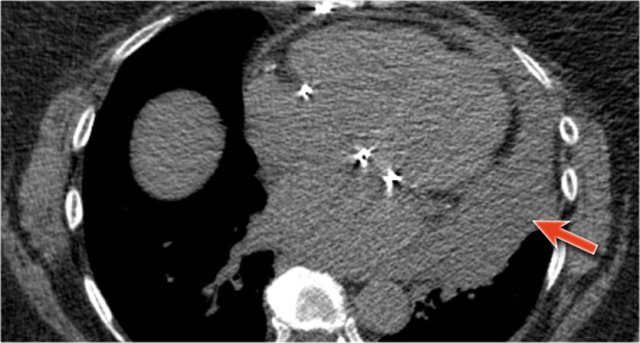

Cardiac incisura

Click image to enlarge.

On the right side of the chest the lung will lie against the anterior chest wall.

On the left however the inferior part of the lung may not reach the anterior chest wall, since the heart or pericardial fat or effusion is situated there.

This causes a density on the anteroinferior side on the lateral view which can have many forms.

It is a normal finding, which can be seen on many chest x-rays and should not be mistaken for pathology in the lingula or middle lobe.

The explanation for the cardiac incisura is seen on this CT-image.

At the level of the inferior part of the heart we can appreciate that the lower lobe of the right lung is seen more anteriorly compared to the left lower lobe.